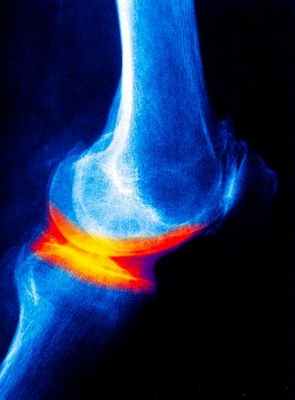

Рентгенологические методы исследования дают, как правило, достаточную информацию о наличии дегенеративных изменениях в суставе. В зависимости от рентгенологической картины проводится и классификация остеоартроза:

- 0 отсутствие рентгенологических признаков остеоартроза

- 1 стадия – кистозная перестройка костной структуры ткани появление маленьких остеофитов признаки линейного остеосклероза

- 2 стадия остеосклероз, более выраженный и появляются признаки сужения суставной щели.

- 3 стадия выраженный остеосклероз остеофиты становятся большими, суставная щель значительно сужается.

- 4 стадия остеофиты более массивные суставная щель практически не визуализируется деформация эпифизов костей их уплощение.

Рентгенологическое исследование суставов.